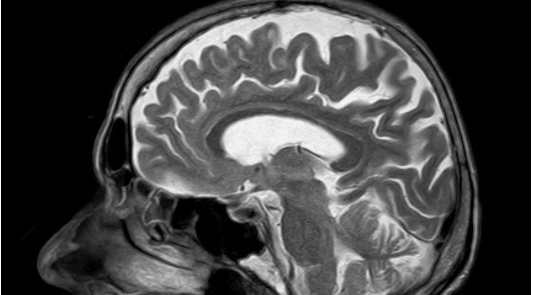

82.治疗和预防脑中风的小秘方:

牛黄祛风汤。地骨皮10克、丹参10克,以上药物煎汤冲服牛黄或人工牛黄1克。如果热像明显的人还可以加3克竹沥水。

平时吃一些核桃、山楂、三七粉也可以起到养脑、健脑的作用。核桃每天吃2-4个,食用过多会碍胃。每天还可以用5~6片山楂泡水,冲服三七粉1克。